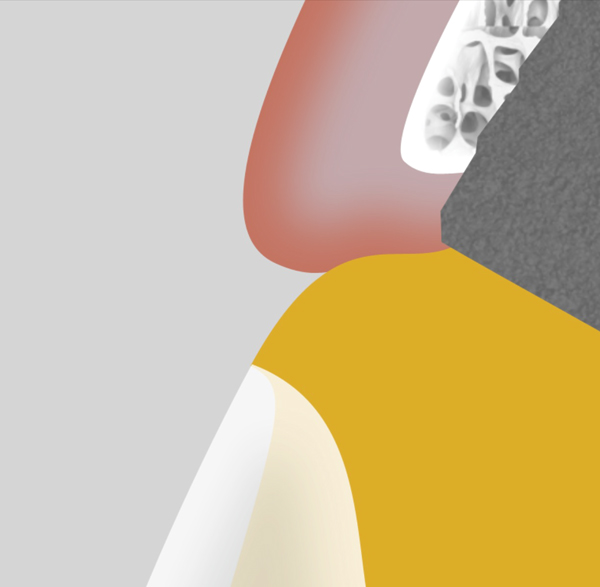

The emergence profile is the portion of the abutment from the head of the implant to the free gingival margin, and it has significant impact on the shape and position of the soft tissue. Generally, a larger diameter emergence profile will compress the soft tissue and move it apically (Figure 5), while a narrowed emergence profile will allow the soft tissue to drape in a more coronal position (Figure 6). Neither design is indicated for all situations, and the design must be based on the needs of the particular clinical scenario.

Fig 5. The “over-contoured” abutment design will displace the soft tissue apically. This design can be used strategically to reposition the peri-implant tissue to its desired position.

Figure 5

Fig 6. Useful in conjunction with immediate load scenarios, the “under-contoured” abutment design allows space for a potential increase in soft-tissue volume or a draping of tissue coronally. This design is created in the provisional restoration and left in position for at least 4 months.

Figure 6